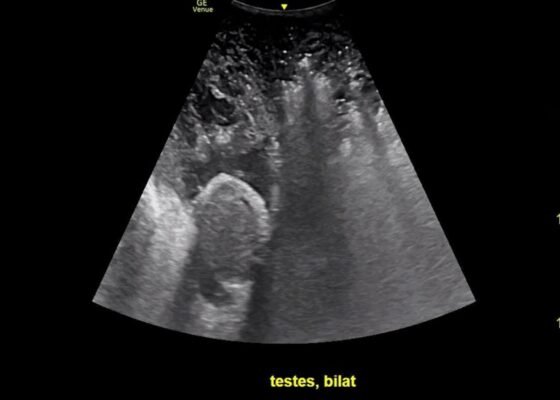

Using Point-of-Care Ultrasound to Expedite Diagnosis of Necrotizing Fasciitis: A Case Report

DOI: https://doi.org/10.21980/J85051A consultative scrotal ultrasound was performed, which was read as showing a small right hydrocele, small bilateral scrotal pearls, and normal-appearing testes. Although present, there was no mention of subcutaneous air suggestive of NF, seen in figure 1 as punctate hyperechoic foci (arrowhead) with ring-down artifact known as dirty shadowing (arrow). Also, subcutaneous thickening (asterisk) and free fluid (arrow) were seen as shown in figure 2, although their clinical relevance was not recognized in the radiologist's final report. Figure 3 shows an abdominal and pelvic CT that re-demonstrates subcutaneous air in the scrotum and lower abdomen (arrow) as well as fascial thickening of the perineum and free intra-abdominal air. After these images, the patient was transferred to our hospital for further management. Almost immediately after the patient's arrival, POCUS was employed. As seen in figures 4, we were able to identify in just a few minutes extensive subcutaneous air accompanied by dirty shadowing, as well as re-demonstration of subcutaneous thickening, fluid collections, and a right hydrocele. Even without the outside hospital's CT, the sonographic findings were highly suggestive for the diagnosis of NF of the perineum, also known as Fournier’s gangrene.